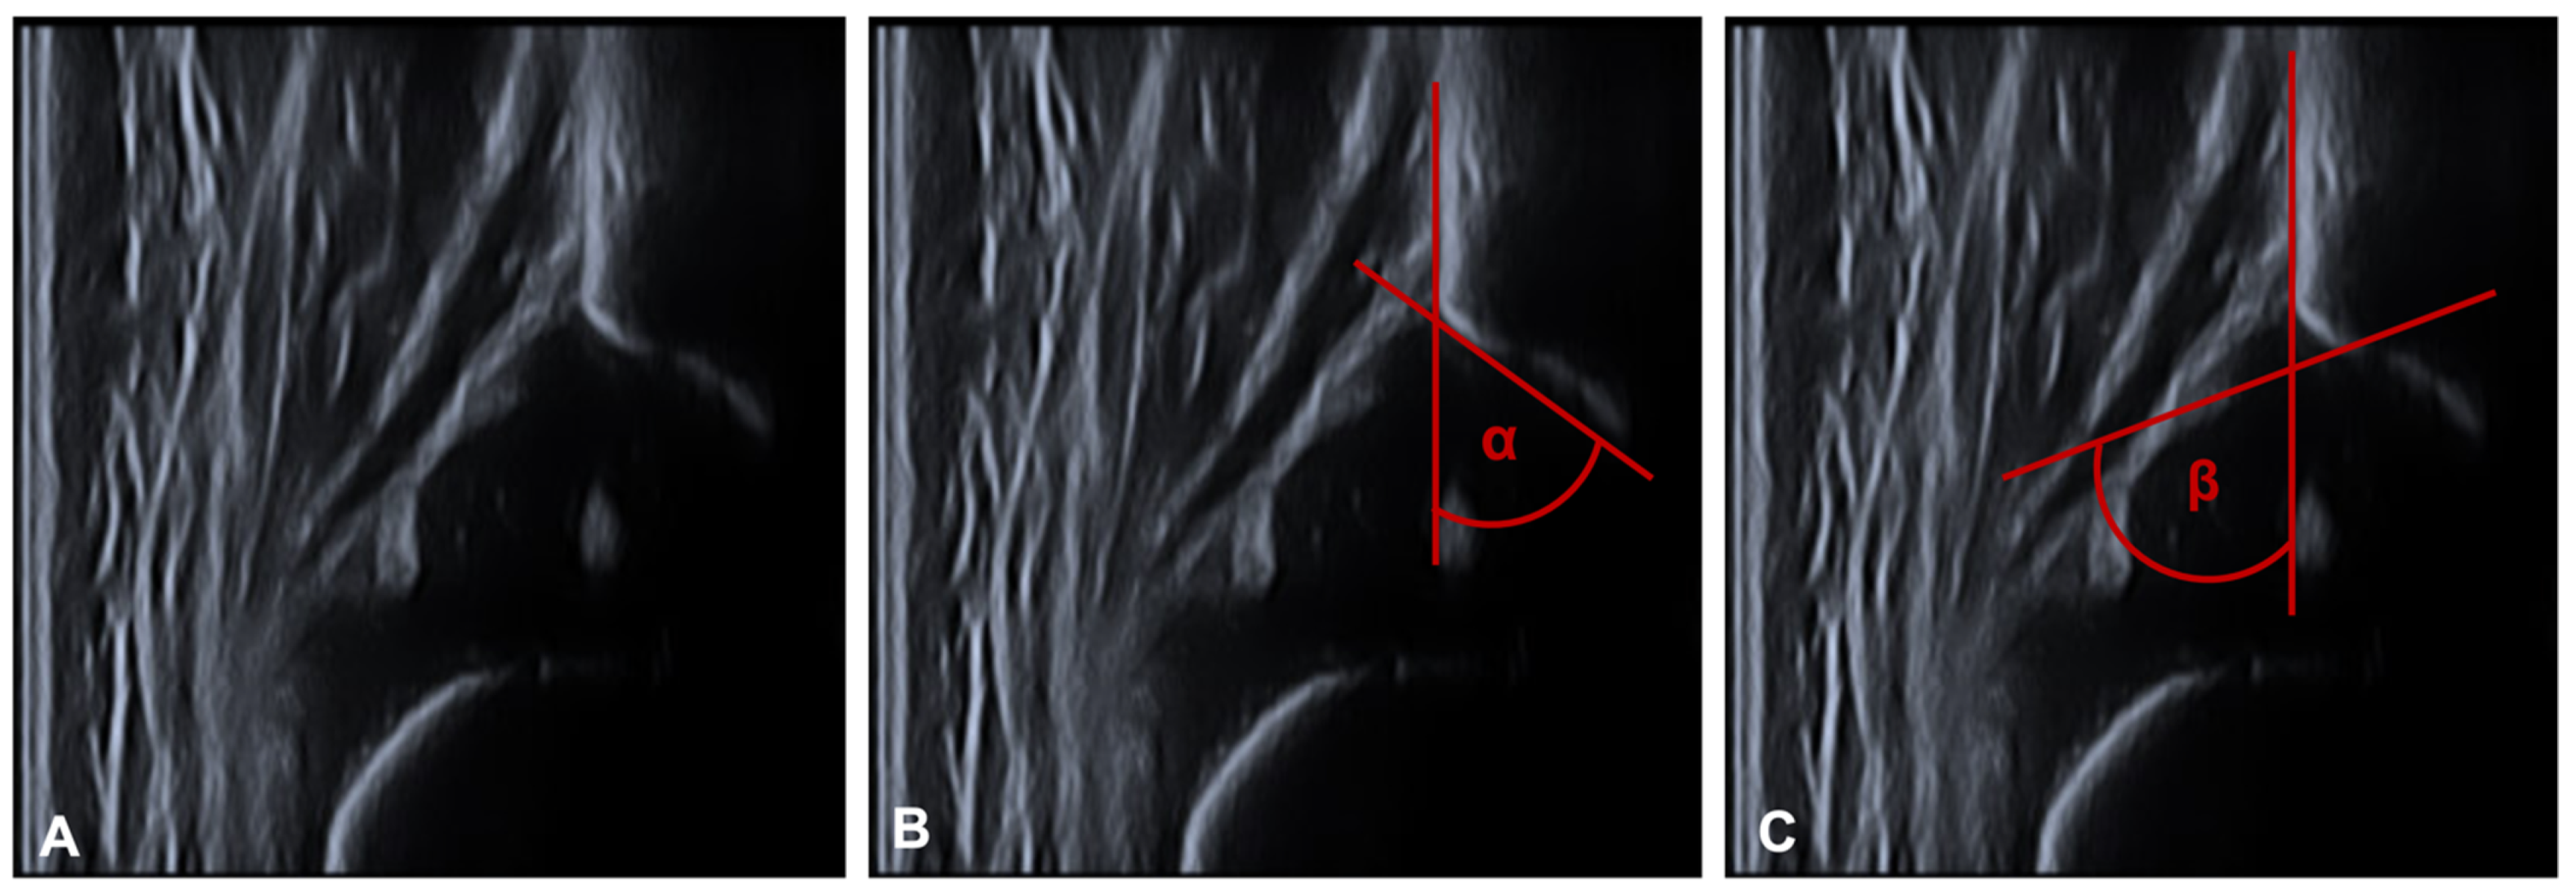

Ultrasound was performed with the Graf technique [33,34]. The child is placed in a lateral position in a positioning tray and examined with a linear ultrasound transducer. This is applied to the greater trochanter in the longitudinal axis of the child and produces a frontal section through the acetabulum. After anatomical identification and usability testing, the α- and β-angles are determined (see Figure 3). The tangent to the os ilium is the baseline for both angle determinations. Two guide lines are added to this baseline to measure the bony acetabular roof angle α (bone angle) and the cartilaginous acetabular roof angle β (cartilage angle). For the latter, a connecting line (display line) is drawn between the bony acetabular notch (turnover point) and the centre of the acetabular labrum. The bony notch is located at the point where the acetabulum changes its profile from concave to convex. For the α-angle, a tangent is drawn to the bony acetabulum starting from the lower edge of the os ilium.

Figure 3.

Shows the measurement of the α- and β-angle. (A) plain ultrasound image for anatomical identification and usability testing. (B) The tangent to the os ilium is the baseline for both angle determinations. For the α-angle, a tangent is drawn to the bony acetabulum starting from the lower edge of the os ilium (C) For the latter, a connecting line (display line) is drawn between the bony acetabular notch (turnover point) and the center of the acetabular labrum. The bony notch is located at the point where the acetabulum changes its profile from concave to convex. The angle between the two lines is called β-angle.